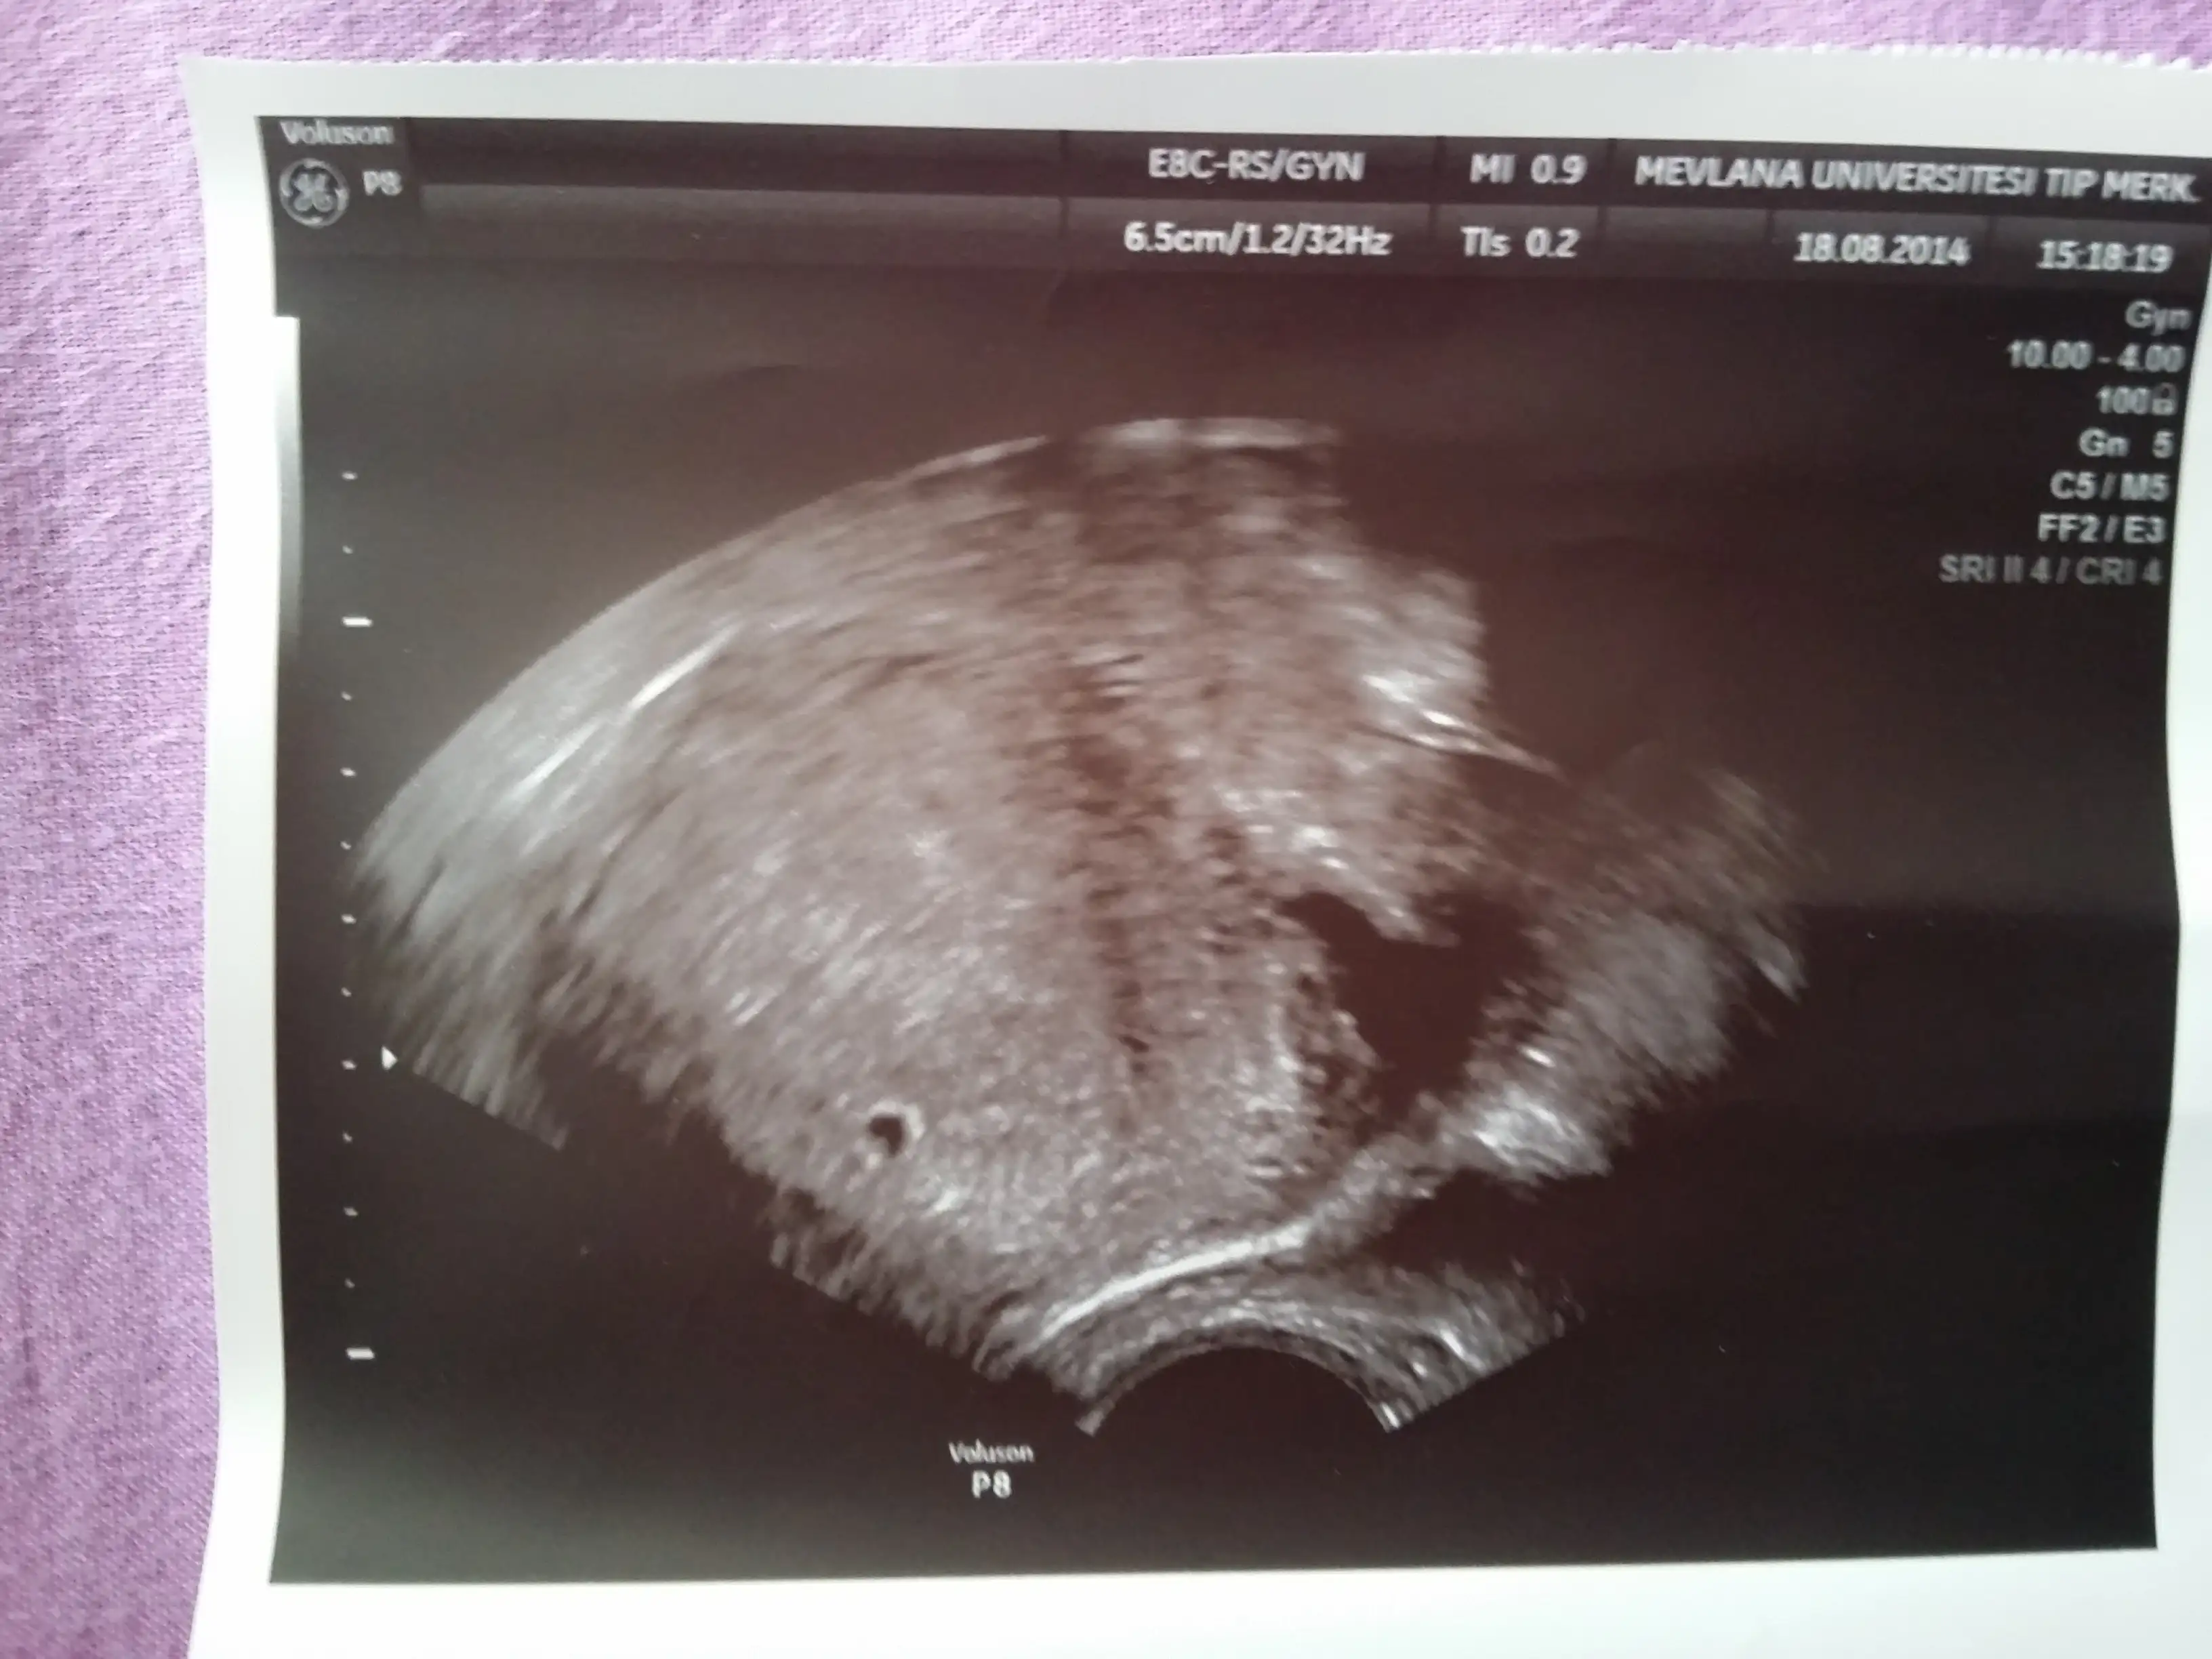

Haftaya cuma cnm inşallah. Baya buyums olr. Doktr dis gebelk vs ddi ama baktk yavasta olsa yukselyo beta hcg beklicz ddik kesemide gördük cok skur. Snnde beta yavasdi sanrminşallah canım sende duyarsın kalp atıslarını senın kontrlun ne zman?

CNM BANA ÖYLE DEMİŞLERDİ KESEYİ GÖRDÜK AMA DR BİŞEY DEMEDİ BENDE SORMADIM KAÇINCI GÜN 2660Kizlar üçüncü defa kan verdim geldim.degerlerim şöyle 306-1220-2660 diye artmis ve ikiz gebelik olabilir dediler çok heyecanliyim degerlerim cokmu yüksek.10 gün sonrada ultrason icin gidicem.